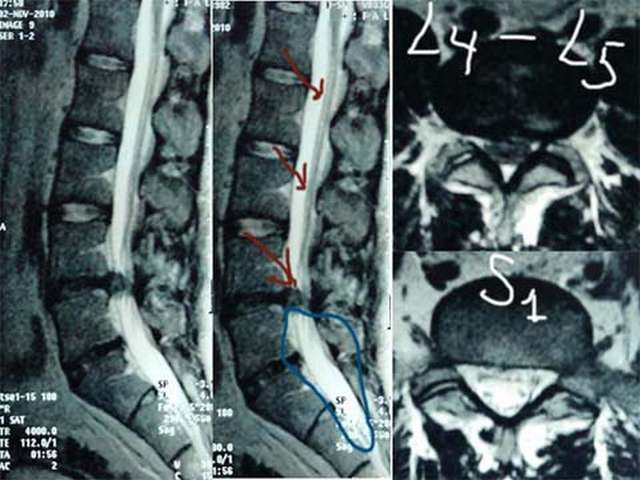

Мужчина 30 лет 3 месяца назад впервые ощутил резкие боли в области поясницы с иррадиацией в правую ногу. Неврологическое обследование выявило негрубую радикулопатию корешка L5 справа. Принимал нимесулид и мидокалм, занимался лечебной гимнастикой по специальной программе – без эффекта. Дважды выполнялась селективная корешковая блокада L5 справа – без эффекта. Выполнена МРТ поясничного отдела позвоночника: выявлена парамедианная грыжа диска L4-L5 0,9х0,4 см. Кроме того, специалистами МРТ выявлены признаки врожденного синдрома натянутого спинного мозга (tethered cord syndrome): спинной мозг прослеживается до уровня S2 позвонка и заканчивается в липоме, окружающей концевую нить на уровне S3, дистальные отделы дурального мешка расширены, конус спинного мозга имеет атипичную вытянутую форму. При дополнительном целенаправленном опросе было установлено, что пациент рос и развивался нормально, активно занимался споротом, участвовал в соревнованиях и до 30 летнего возраста болей в позвоночнике не испытывал. Недержания мочи и кала никогда не отмечал. Чувствительность в области промежности не нарушена. Тонус анального сфинктера нормальный. Анальный рефлекс сохранен. Вопросы: действительно ли мы имеем местно с врожденным синдромом натянутого спинного мозга, который выявлен случайно после появления грыжи диска? Хирургическое лечение следует ограничить микрохирургической дискэктомией или необходимо дополнительно рассечение концевой нити с удалением липомы?